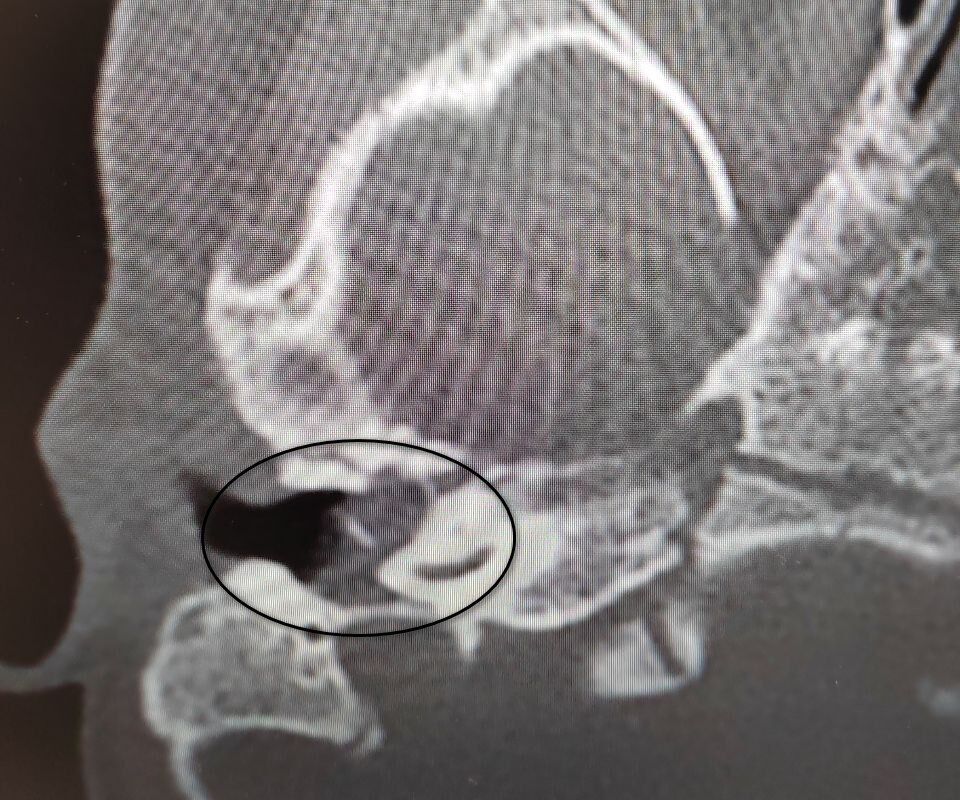

Девочка поступила в оториноларингологическое отделение больницы с хроническим гнойным средним отитом и подозрением на врожденную холестеатому барабанной полости - кистозное патологическое образование в среднем ухе. Врачи отметили, что подобное заболевание крайне редко диагностируется у детей в столь раннем возрасте.

"Холестеатома опасна тем, что может привести к рецидивирующему гноетечению и разрушению структур среднего уха, отвечающих за слух", - пояснили в пресс-службе ведомства.

После обследования и подтверждения диагноза пациентку направили на операцию, в ходе которой хирурги удалили у нее холестеатому, провели декомпрессию лицевого нерва и восстановили механизм звукопроведения.